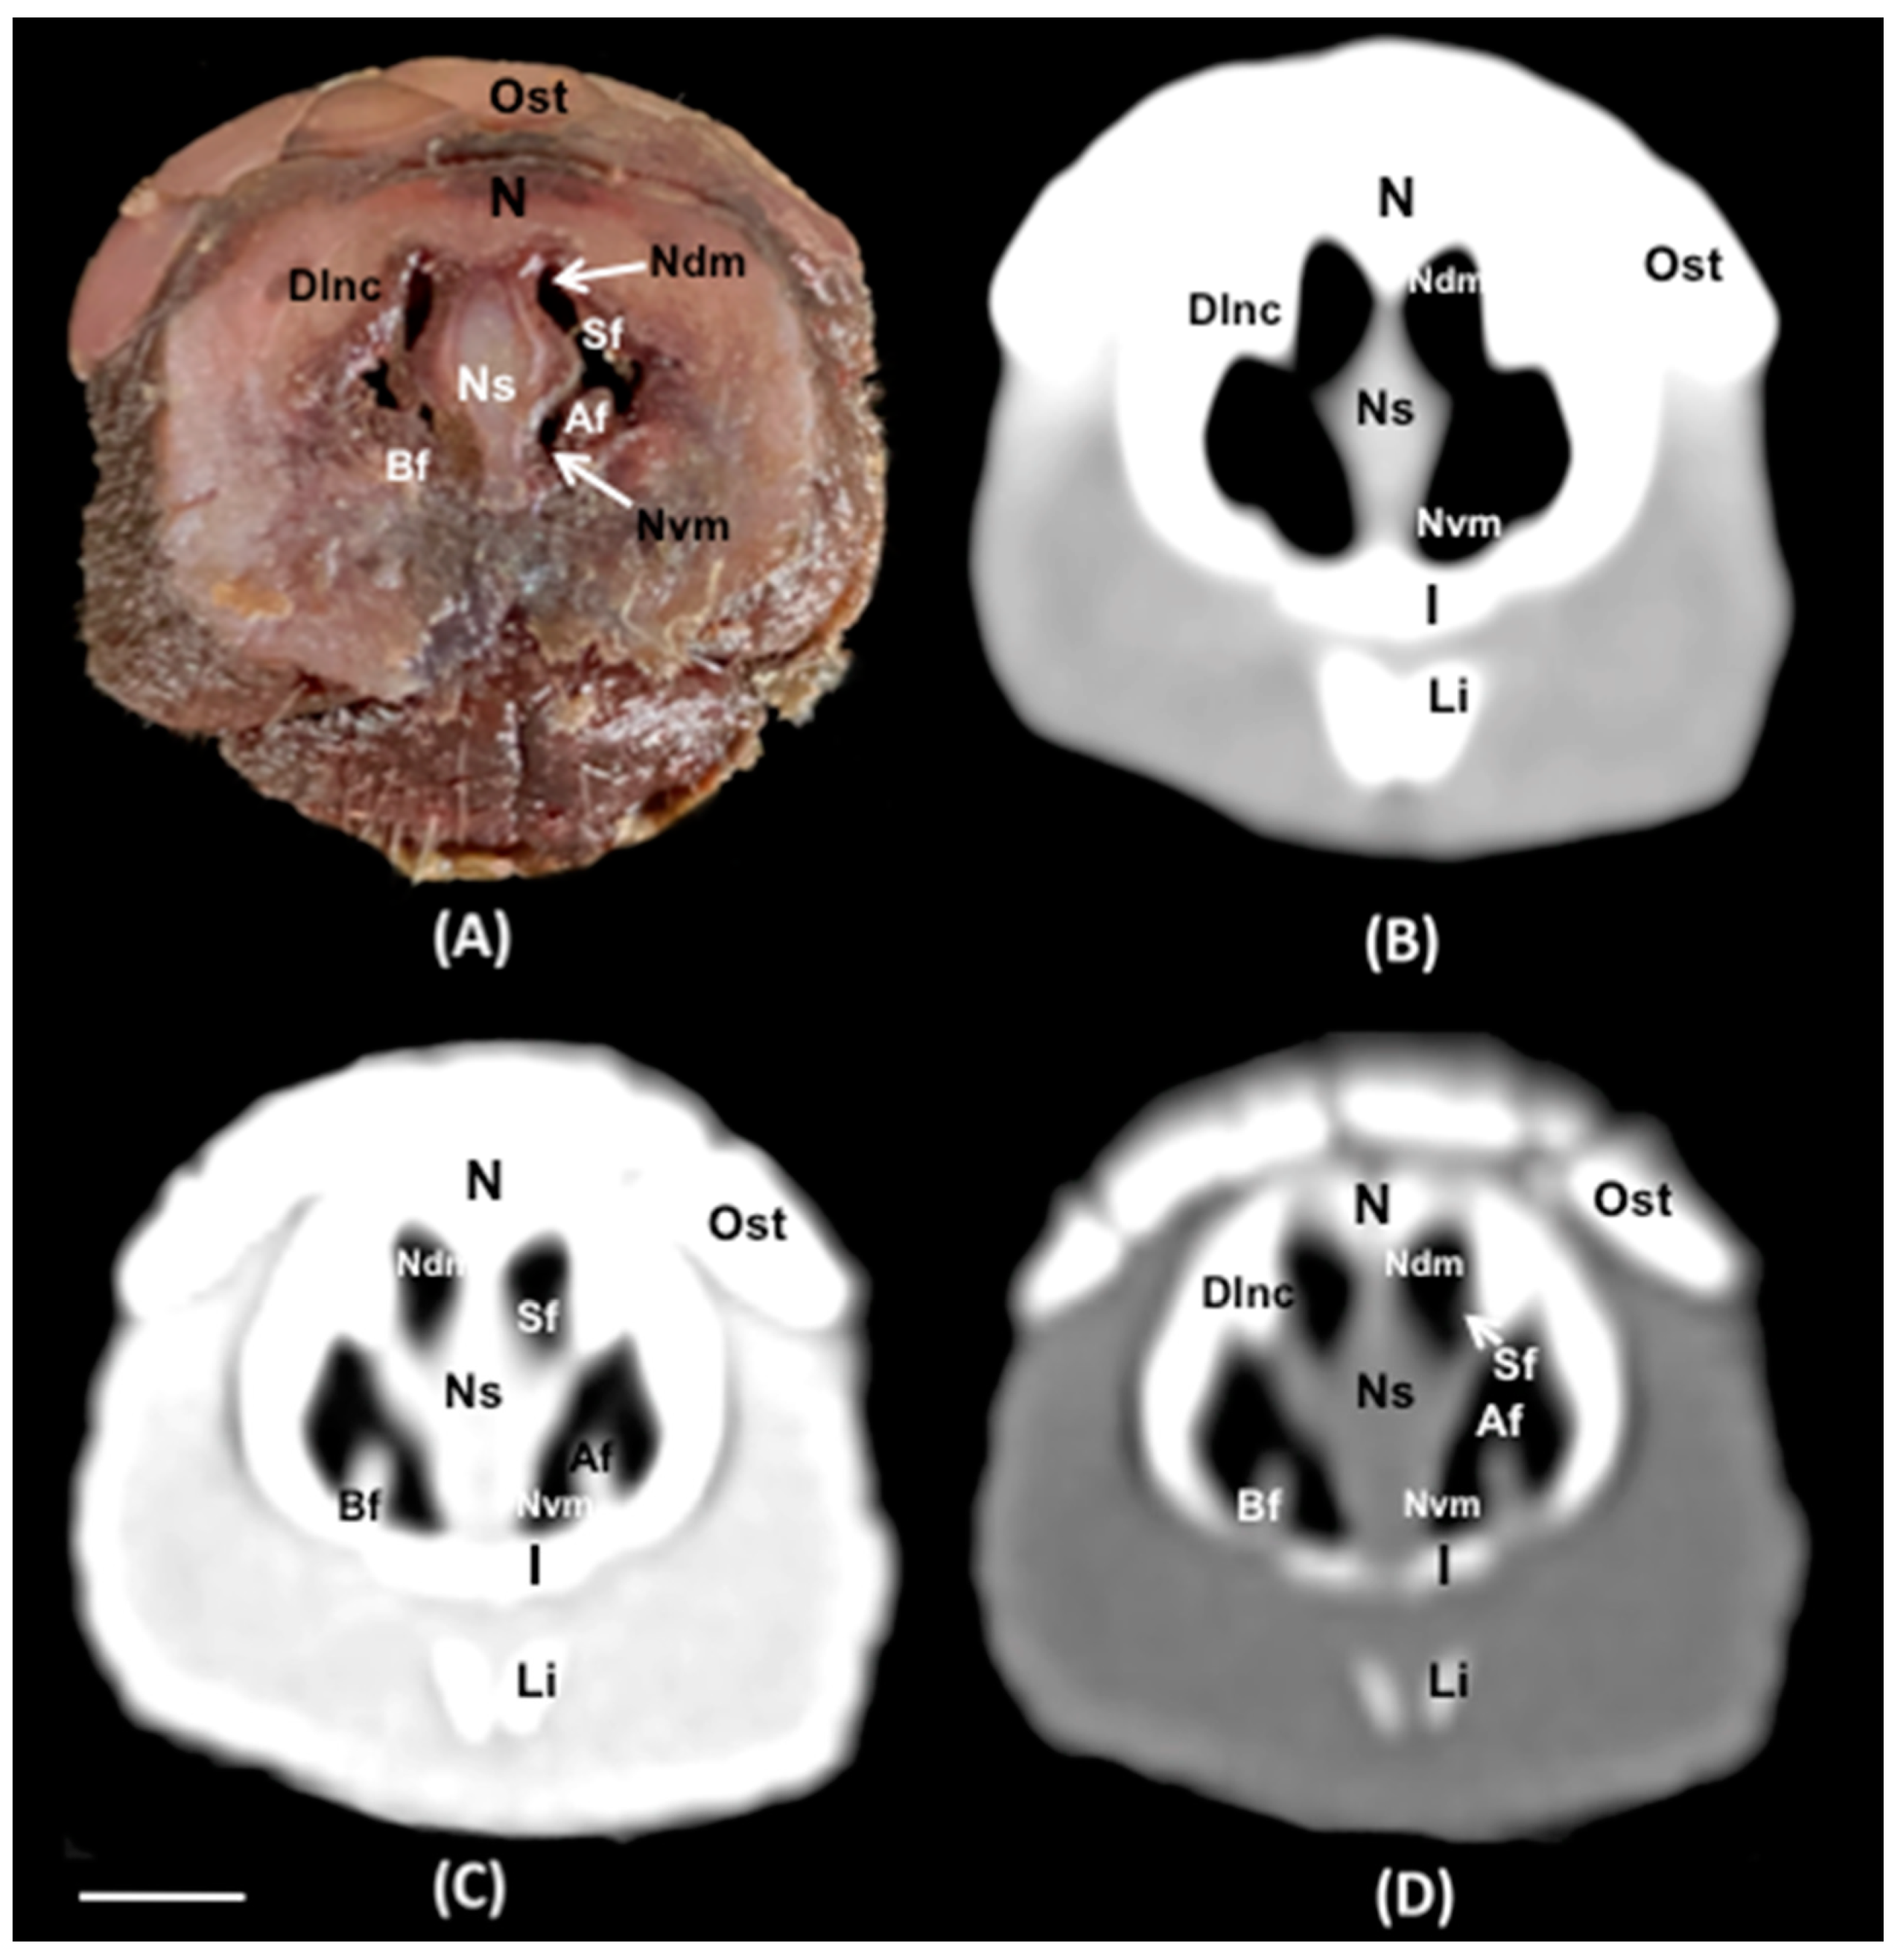

3.1. Anatomical Sections

3.2. Computed Tomography (CT)